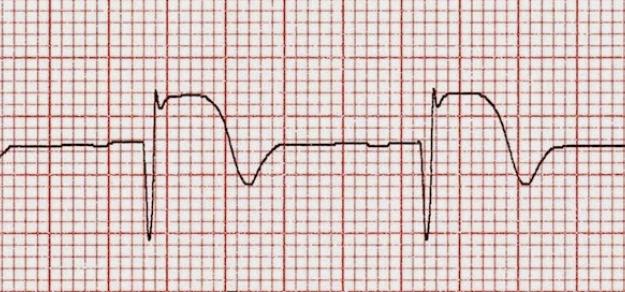

Uno de cada tres pacientes es derivado para reperfusión miocárdica, pero los derivados tienen menor probabilidad de recibir tratamiento de reperfusión y menor utilización de angioplastia primaria. Una mejor articulación de las redes podría mejorar el acceso y disminuir la morbimortalidad. Revista Argentina de Cardiología, 2017 Nº 2

- Cardiología

- Cardiol